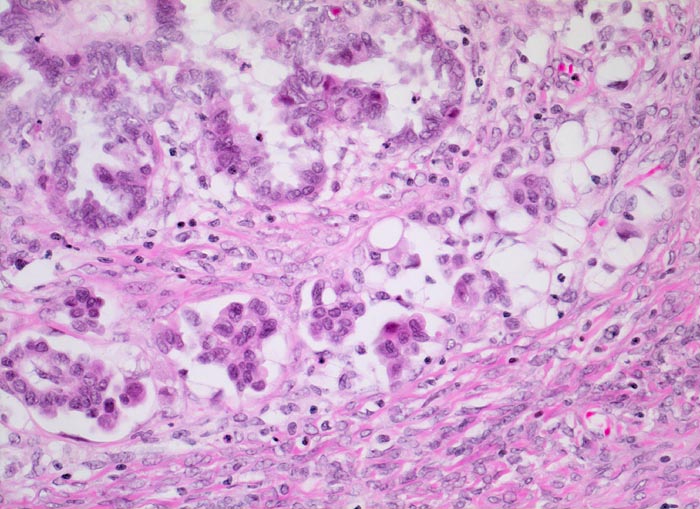

PathoPic ID 4479 - mikroinvasives serös papilläres Ovarialkarzinom

mikroinvasives serös papilläres Ovarialkarzinom

maligner Tumor

Ovar

An umschriebener Stelle invadieren

kleinere Zellgruppen und

Einzelzellen das an dieser Stelle aufgelockerte Stroma.

Histologie

200